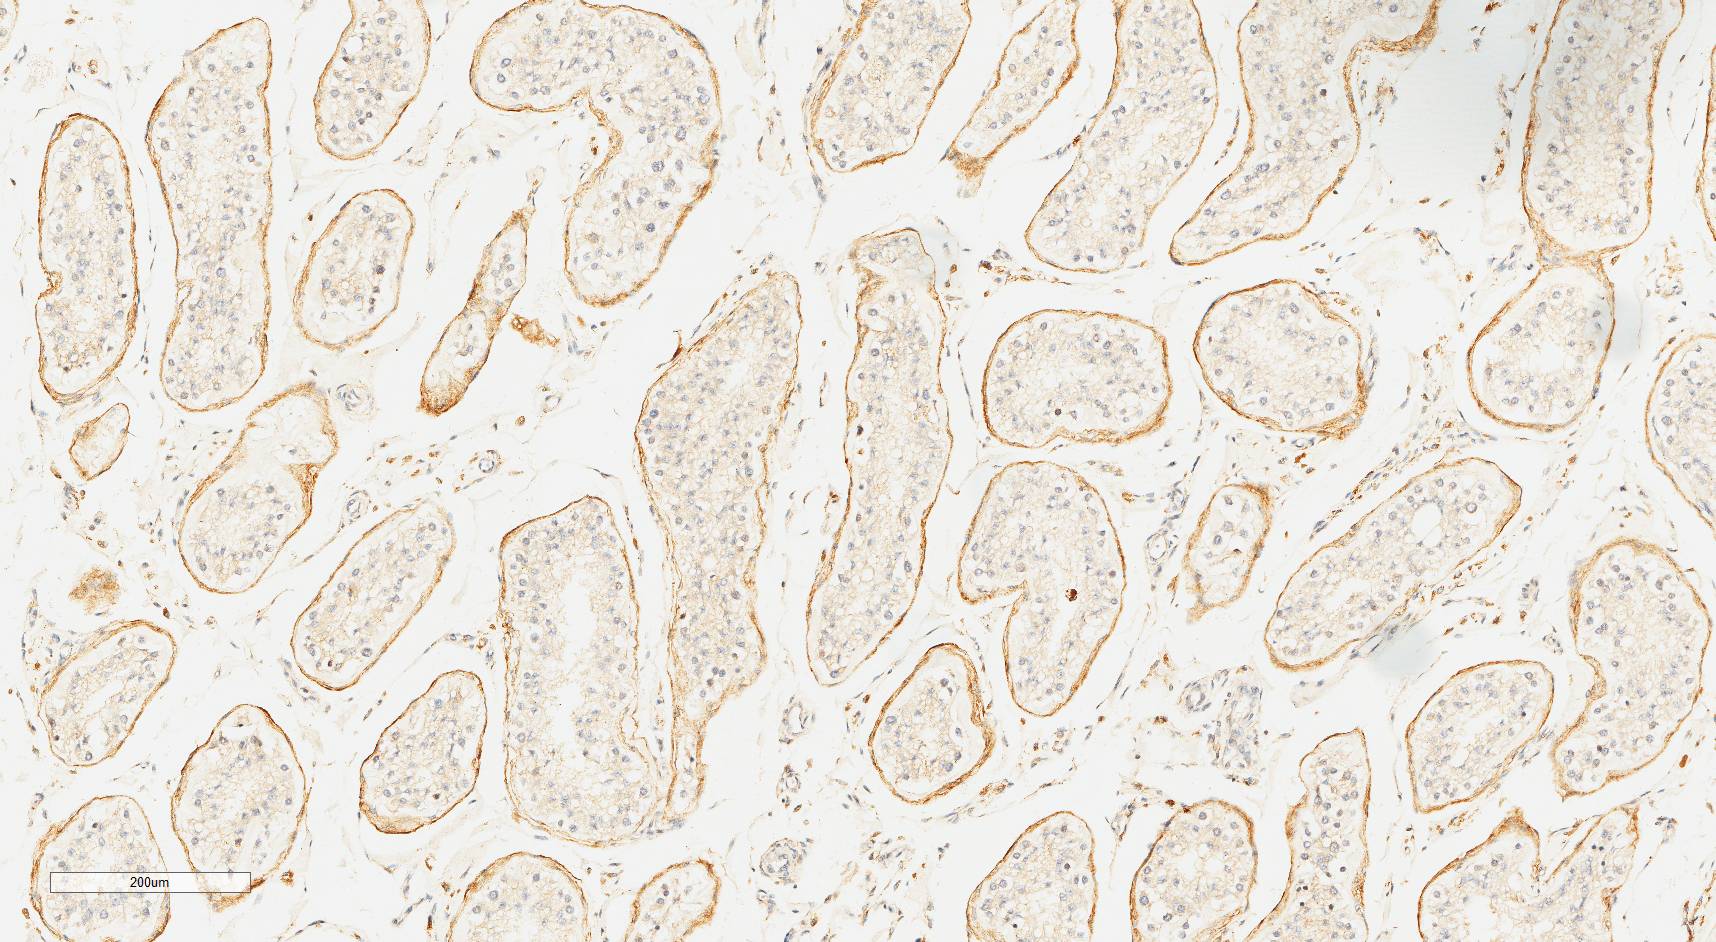

Laminin N terminus alpha31 (LaNt a31) is a really interesting laminin-related protein that the Hamill lab has been investigating for a while. Until recently, our studies focused entirely on the epithelial tissues of the skin, the surface of the eye and oral squamous cell carcinoma. However, we’ve always known that this relatively unstudied protein is also expressed by other tissues. As a first (and really important) step to understanding what this protein’s role is in tissue function, we used our new mouse monoclonal antibodies against the human form of LaNt a31 to screen a wide-range of human tissues.

Below you can see some of our favourite images from the selection. Click on an image to view as a slideshow.

You can see the whole story in the paper by Lee Troughton et al., available here.